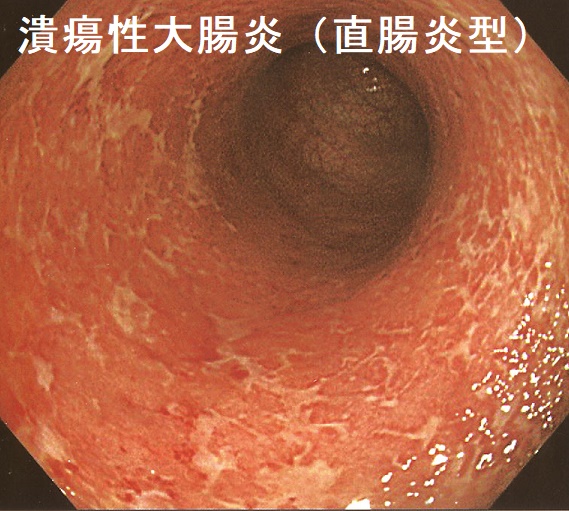

潰瘍性大腸炎(UC)は大腸の炎症で、直腸から連続して口側に向かい病変が広がります(一方、クローン病(Crohn 病)は小腸と大腸の炎症です)。病変の範囲により、①全大腸炎(最多)、②左側大腸炎、③直腸炎に分けられます。

副腎皮質ステロイド剤のブデソニドは、泡状で液漏れが少なく、局所作用に優れ、全身副作用も少ないのが特徴。軽症-中等度の直腸型やS状結腸型に有効。